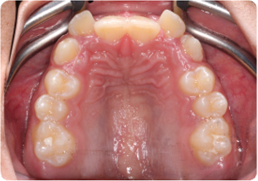

Each case shows the front view and an arch or side view, before and after BioLign Method-guided treatment.

Crowding with irregular gaps resolved into even alignment